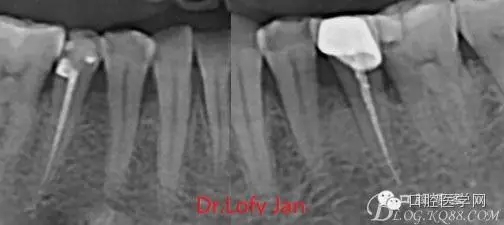

前言:自己做的一些曲面斷層片在未試尖根管治療中的病例整理,發(fā)現(xiàn)問題很多包括自身的,技術(shù)的,還有設(shè)備的問題,予以總結(jié)整理并期待進一步提高。

根管治療術(shù)是牙體牙髓疾病治療中最復雜和最關(guān)鍵的治療項目。根管充填材料抵達根尖、并能嚴密堵塞根尖孔,是確保根管治療效果的關(guān)鍵指標。為了保證根管充填到位,醫(yī)生需要在術(shù)前照牙片以了解牙根根管的數(shù)量、彎曲程度和長度,在術(shù)中有時需要插針照牙片來精確測量根管長度,術(shù)后必須照牙片以確定是否根管充填到位,如果欠填或超填,就需要重新充填、重新照牙片確認,直到根管充填到位。所以,在患者接受根管治療時有時會反復照牙片。

《數(shù)字化根尖片、曲面斷層片、CBCT測量牙齒長度準確性的比較研究》文中顯示:平行投照數(shù)字化根尖片影像長度和牙齒實際長度之間無顯著性差異(P0.05);數(shù)字化曲面斷層片影像長度和牙齒實際長度之間有顯著性差異(P0.05),平均失真率為17.05%。CBCT冠狀面測量結(jié)果中除上頜前磨牙區(qū)、下頜前磨牙區(qū)與真實長度差異無統(tǒng)計學意義(P0.05)外,其余6個分區(qū)差異均有統(tǒng)計學意義(P0.05);矢狀面測量結(jié)果中上頜磨牙區(qū)、下頜磨牙區(qū)、下頜前磨牙區(qū)、下頜尖牙區(qū)、下頜前牙區(qū)與真實長度比較差異均有統(tǒng)計學意義(P0.05)。結(jié)論平行投照數(shù)字化根尖片較曲面斷層片和CBCT能更加精確地反映牙齒的真實長度。

病例分析:曲面斷層片在x線輔助診斷與檢查中目前大多數(shù)文獻和著作都建議只能作為初診拍片檢查手段,不能作為終末疾病的確診與手術(shù)療效的評價指標,臨床大部分中小型門診都因為設(shè)備不齊全導致信息偏差很大。